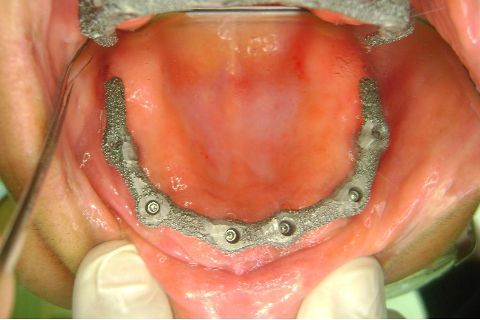

Atualização do caso clínico que já postei, "REABILITAÇÃO EM MAXILA ATRÓFICA COM IMPLANTES", um caso que inclui expansão do rebordo estreito com cinzel e martelo, expansores rosqueáveis, enxerto e instalação dos implantes distais inclinados tangenciando seio maxilar. Inclui esvaziamento do forame nasopalatino e preenchimento com biomaterial para instalação de dois implantes próximos dele. Cirurgia realizada em única sessão, com instalação dos 6 implantes. Para os colegas que não conheceram e/ou esqueceram da apresentação, este é o resumo do caso na fase cirúrgica.http://www.youtube.com/watch?v=BtvexFexRPA&hd=1

FASE PROTÉTICA DA REABILITAÇÃO EM MAXILA ATRÓFICA...incluindo a reabertura, instalação dos minipilares e PTR provisória reembasada sobre os cilindros de proteção.